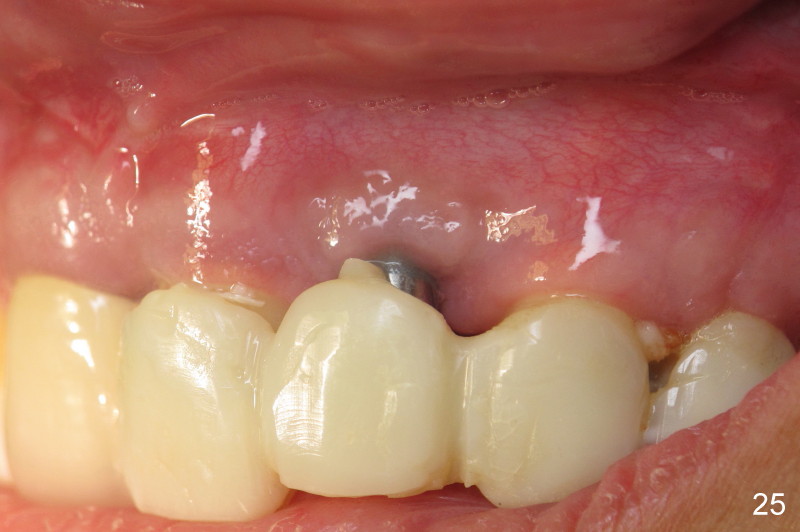

Segmental Osteotomy for Misplaced Implant

This corrective surgery was performed by Dr. Bernee Dunson.

Xin Wei, DDS, PhD, MS 1st edition 12/21/2011, last revision 12/23/2011